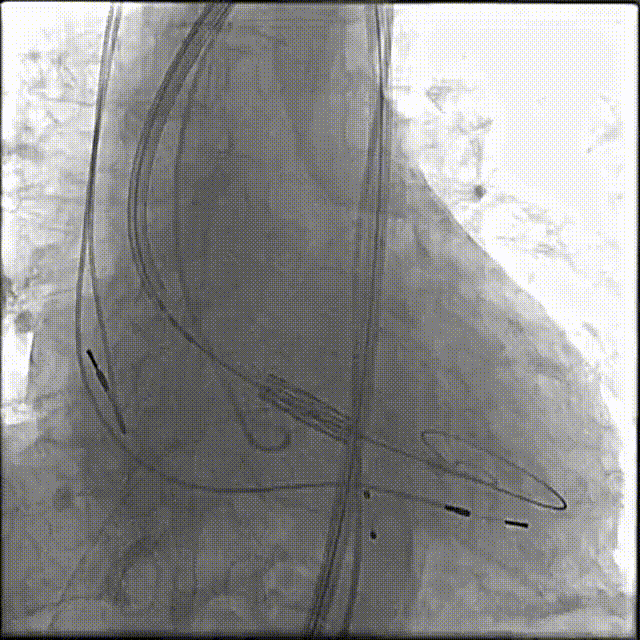

由于患者预扩后没有明显的腰部特征,最终选择常规的26mm瓣膜。使用输送系统装载26mm的SAPIEN 3瓣膜,借助双重调弯功能顺利通过主动脉弓并跨过自体瓣膜,将球囊拉入支架瓣膜内时,因患者重度横位心,回拉时瓣膜支架嵌入推送杆以内,导致球囊难以到位,手术团队反复推送调整,最终顺利到位。

大角度横位心反复推送调整球囊